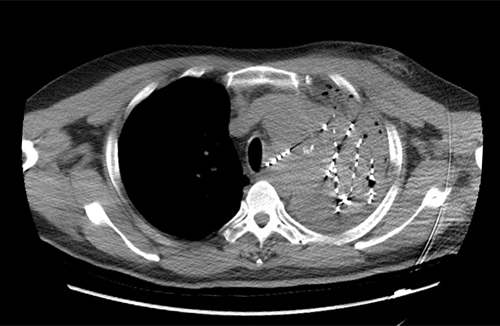

56岁的贵先生确诊左肺鳞癌两年半,两年来先后在多家医院给予放射治疗、多周期化疗、抗血管生成药物及靶向药物治疗等。近期病情再次加重,多次出现大咯血等情况,患者及家属一度绝望,后辗转到临床医学院/附属医院。呼吸内一科医生根据患者病情进行多次讨论,决定在咯血稳定后,为患者实施肿瘤内碘125I粒子植入术。此次手术为该院首例CT引导下肺癌放射性粒子植入术,过程顺利,术后CT显示粒子分布良好,经后续监护及观察,患者无特殊不适,原有胸痛胸闷症状明显缓解,达到治疗预期效果。据悉,碘125I粒子植入术作为组织间近距离放疗的一种新手段,自被证实为治疗肺癌安全有效、无严重副作用的治疗手段以来,国际国内正逐步开展,打开了肿瘤微创治疗的新篇章,临床医学院/附属医院呼吸一科紧跟学科发展,积极引进,为癌症患者带来了福音。